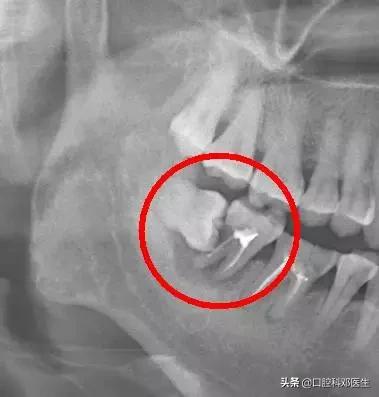

口说无凭,上病例。来看下面这例

智齿祸及邻牙

这种情况就因为没及时拔除智齿,最终的结果就是把邻牙也拖下水,两颗牙齿一起报销,旁边的第二恒磨牙本来就容易因为清洁不彻底龋坏的好么,还要无端被拖着陪葬,真是生存不易。更惨的是,邻牙拔除之后,还必需要装上一颗种植牙补上(我会告诉你装一颗种植牙花费上万是很正常的么),得不偿失啊!!

需要特别注意的是,邻牙病变具有一定的隐蔽性,通常的情况是可能旁边牙齿已经被顶坏了,患者还没有任何感觉,这就需要拍一张口腔 X 光片才能进行准确的诊断。